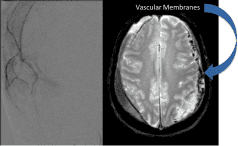

Dr. Brisman is proficient in the use of minimally-invasive, neurosurgical procedures including:

- Microvascular Decompression